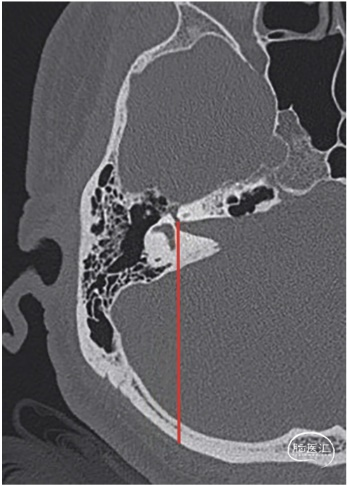

该研究回顾性分析33例取“公园躺椅体位”行乙状窦后开颅切除听神经瘤的患者临床资料。依据患者术前术后的CT,以起始于内听道底、走行于迷路的后方到达枕骨鳞部的内听道底—迷路线(FLL),作为确定开颅骨窗后缘的位置(图1、2、3、4);并用logistic回归模型评估开颅骨窗的位置与内听道底暴露概率的相关性。

图1. CT轴位骨窗像。FLL线(红色)从面神经管开口开始,向后方走行和后半规管的轴线相切。